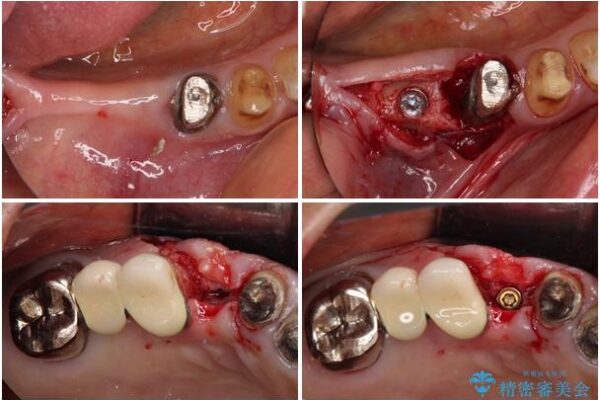

治療途中

• 前歯をきれいにしたい インプラントや部分矯正を用いた総合歯科治療 治療途中画像